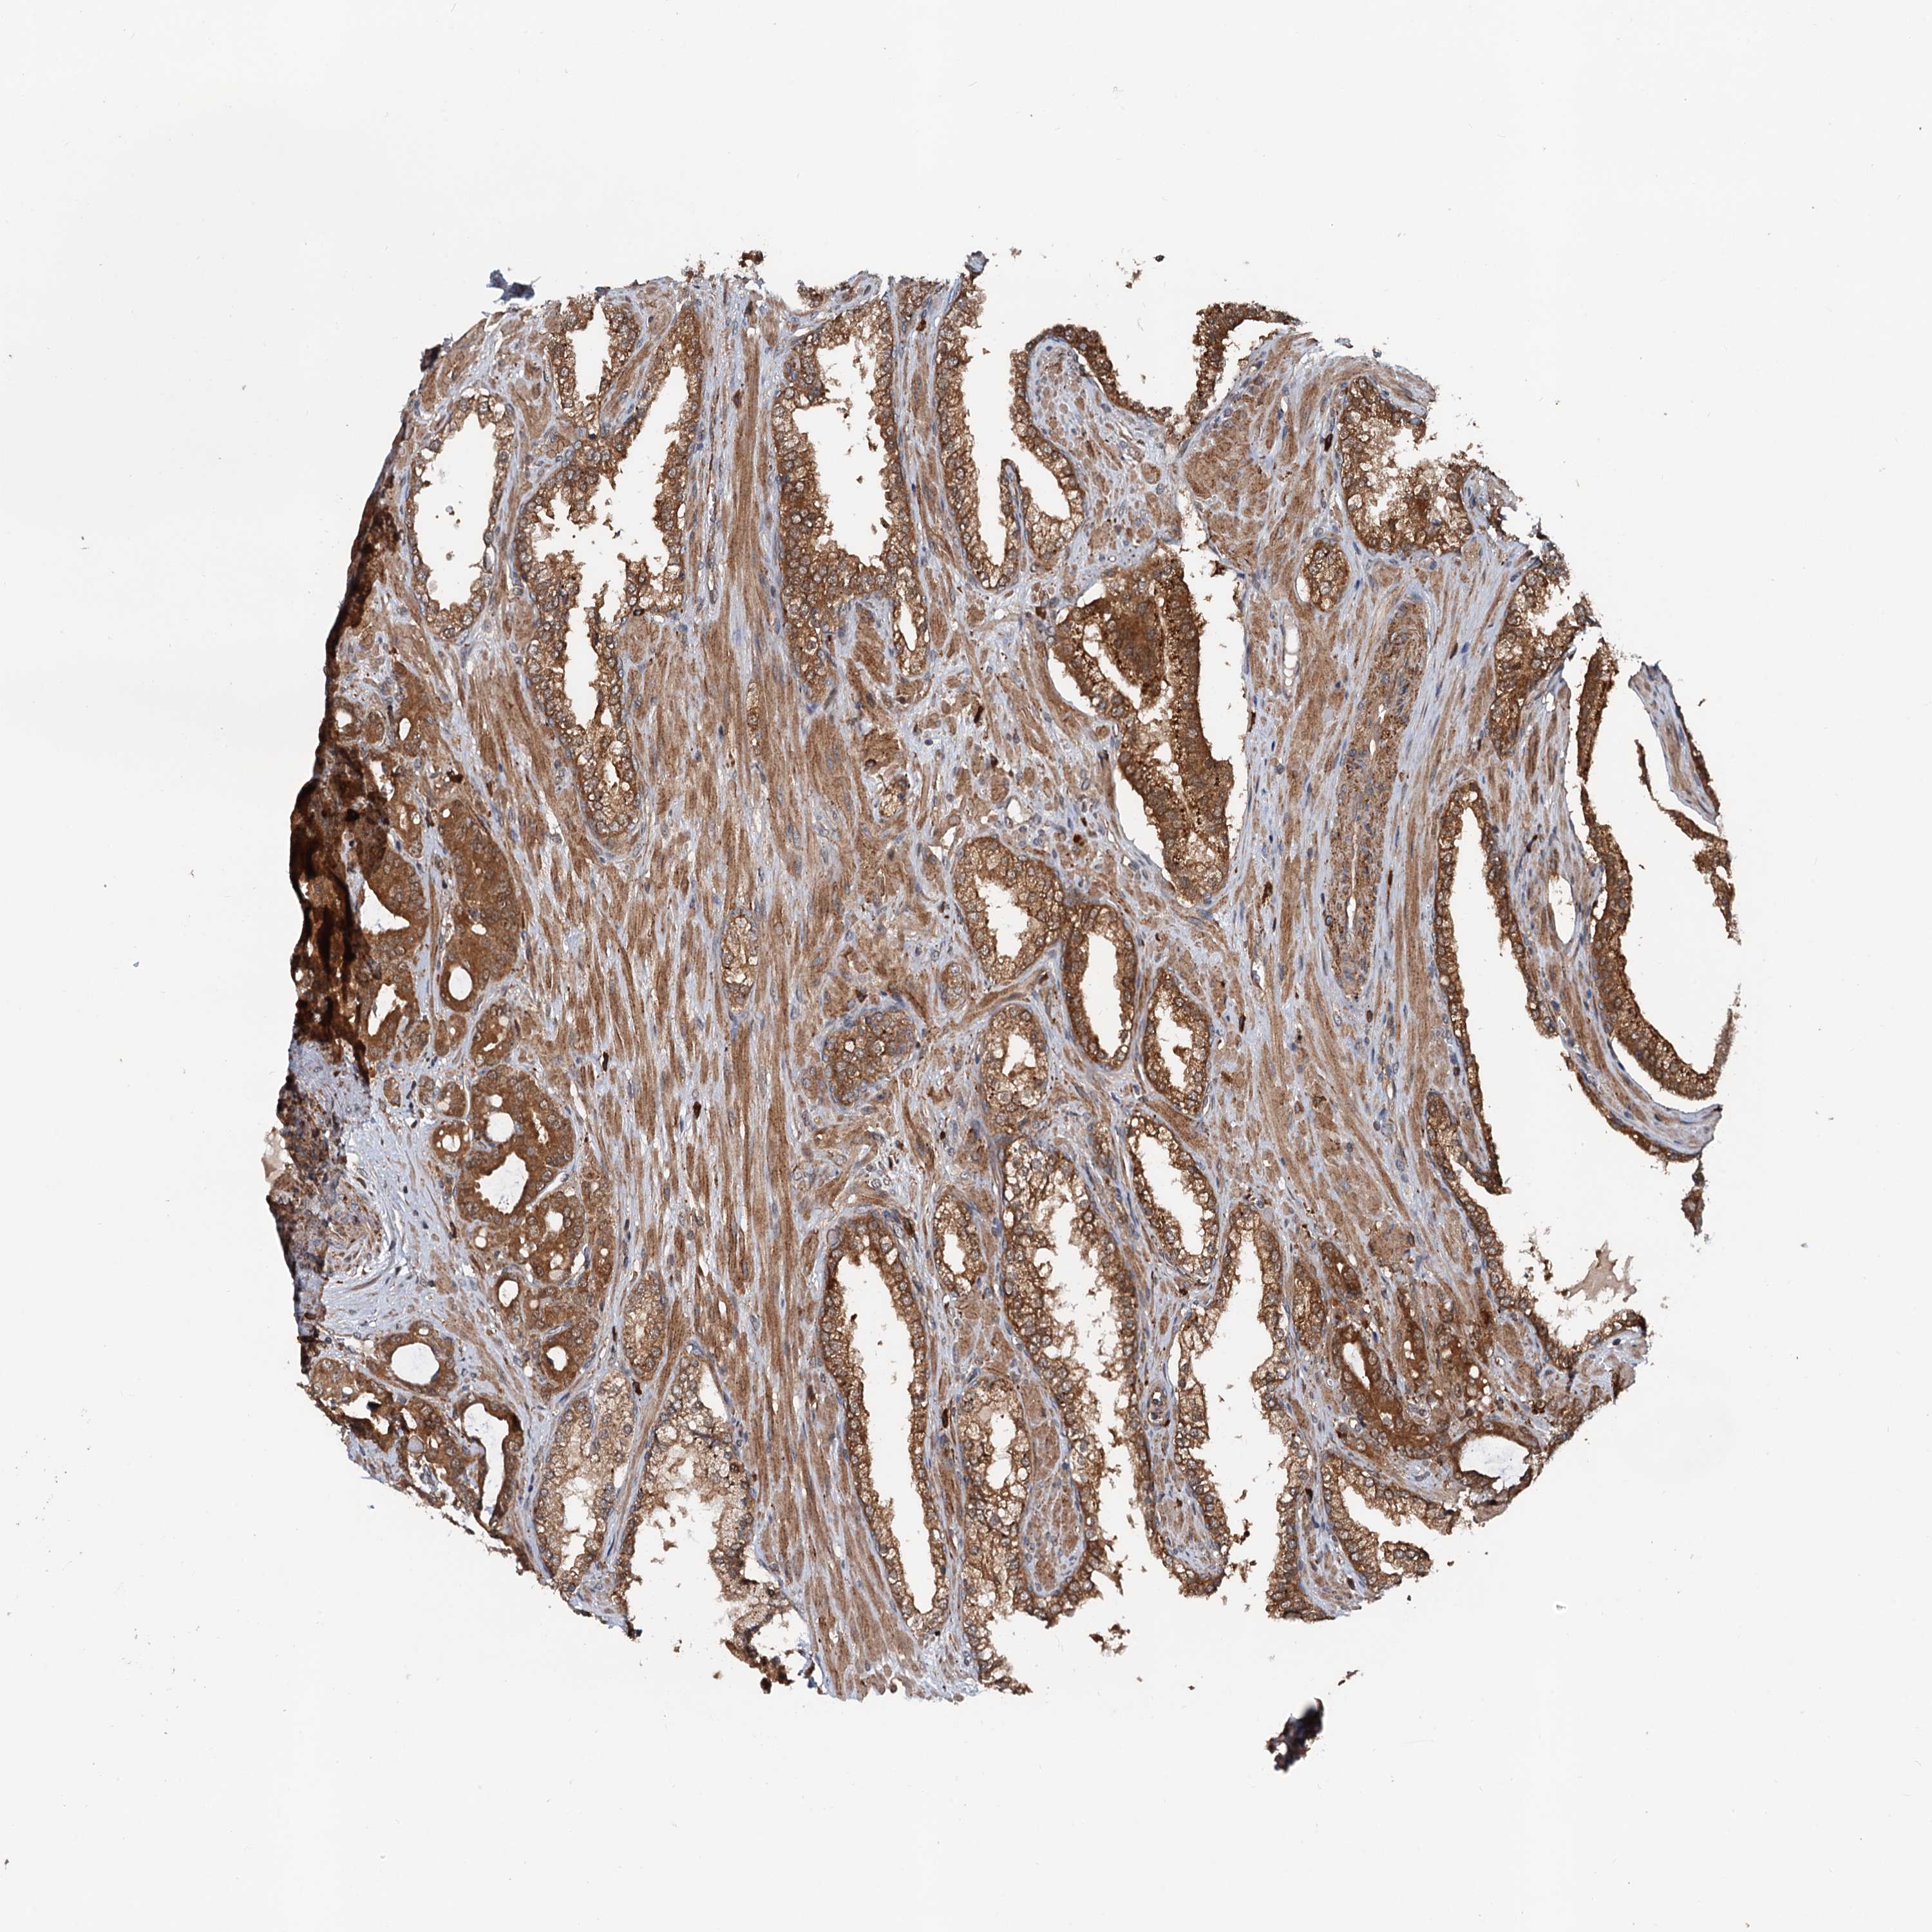

PROSTATE CANCER - Protein expressioni

A mouse-over function shows sample information and annotation data. Click on an image to view it in a full screen mode. Samples can be filtered based on level of antibody staining by selecting one or several of the following categories: high, medium, low and not detected. The assay and annotation is described here.

Antibody stainingi

Antibody staining in the annotated cell types in the current human tissue is reported as not detected, low, medium, or high, based on conventional immunohistochemistry profiling in selected tissues. This score is based on the combination of the staining intensity and fraction of stained cells.

Each image is clickable and will lead to virtual microscopy that enables deeper exploration of all samples and also displays staining intensity scores, fraction scores and subcellular localization as well as patient and tissue information for each sample.

Antibody HPA039371

Antibody HPA040174

Staining

High

Medium

Low

Not detected

Intensity

Strong

Moderate

Weak

Negative

Quantity

>75%

75%-25%

<25%

None

Location

Nuclear

Cytoplasmic/membranous

Cytoplasmic/membranous,nuclear

Adenocarcinoma, NOS

Adenocarcinoma, High grade

Adenocarcinoma, Low grade